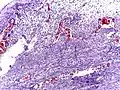

Pathology diagnosis of appendicitis can be made by detecting a neutrophilic infiltrate of the muscularis propria.

Micrograph of appendicitis showing neutrophils in the muscularis propria. H&E stain.